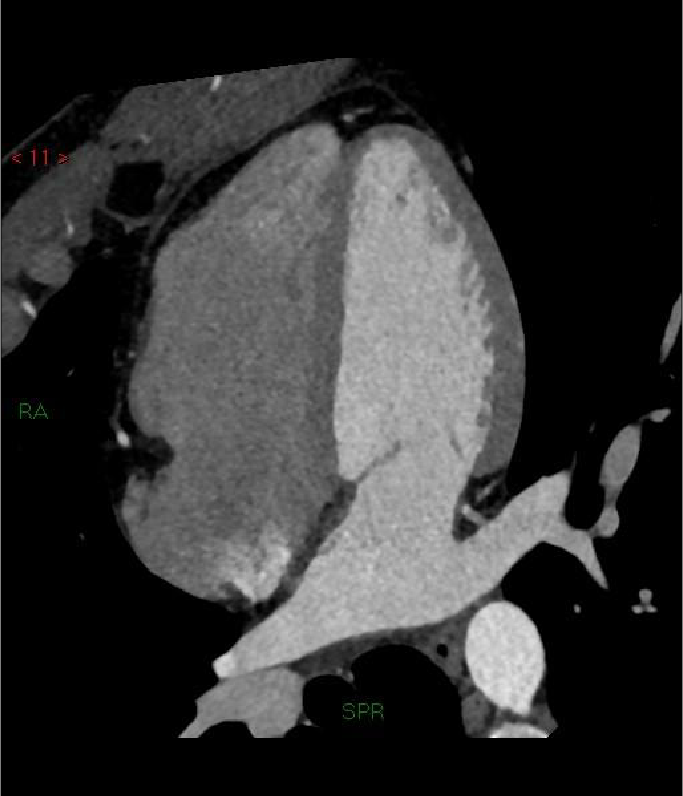

Tomografía cardiaca

Este estudio es adquirido con un tomógrafo de alta velocidad y baja radiación que permite evaluar las arterias coronarias y demostrar la ausencia o la presencia de placas ateromatosas, que son las que ocasionan un infarto (enfermedad arterial coronaria). Mediante la emisión de rayos X es posible obtener imágenes bidimensionales y tridimensionales del exterior y del interior de las arterias coronarias, del corazón y de la función cardiaca.

Una modalidad de la tomografía cardiaca muy utilizada hoy día es el índice de calcio coronario que es útil para identificar oportunamente la presencia de calcio que se asocia con las placas de ateroma que obstruyen tus arterias y ocasionan un infarto. Este estudio se adquiere en menos de un minuto y no se necesita utilizar medio de contraste.

El calcio que se deposita en las arterias coronarias es la “primera señal” que podemos medir antes de que aparezcan los síntomas de la enfermedad y en conjunto con las indicaciones de tu médico, podrás prevenir la progresión de la enfermedad e incluso un infarto.

Cuando es necesario hacer una evaluación mas precisa de tus arterias coronarias la tomografía cardiaca permite, mediante la inyección de contraste por una vena del brazo, estudiar el interior de las arterias y demostrar si existen o no placas que impiden el paso de sangre hacia el corazón, a esta modalidad de la tomografía cardiaca le conocemos como angiotomografía coronaria, que se adquiere en 30 a 60 minutos, y es hoy día el estudio mas confiable para evaluar en forma no invasiva las arterias que nutren al corazón y que cuando se enferman pueden ocasionarte un infarto.

Existen otras indicaciones de la tomografía cardiaca que permiten evaluar las válvulas del corazón y de los grandes vasos como la aorta.